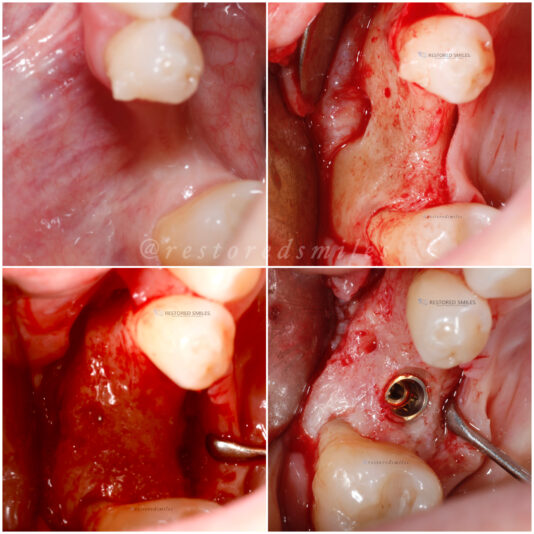

• This case was a tricky one. Sometimes, we just need to do the best with what our patients anatomy gives us. Patient was referred to me wanting an implant and there wasn’t much to work with and oh yeah, the mental foremen was smack dab in the middle of our sight.

With the help of some buccal plate decorticating, a tenting screw, and some CGF/PRF…

This shows how we dealt with the complication of a buccal perforation. Luckily, the patient had sufficient width so we removed the implant and placed another implant lingual to that site with better buccal lingual agulation. We then bone grafted the site and perforation and secured a resorbable collagen…

Read more